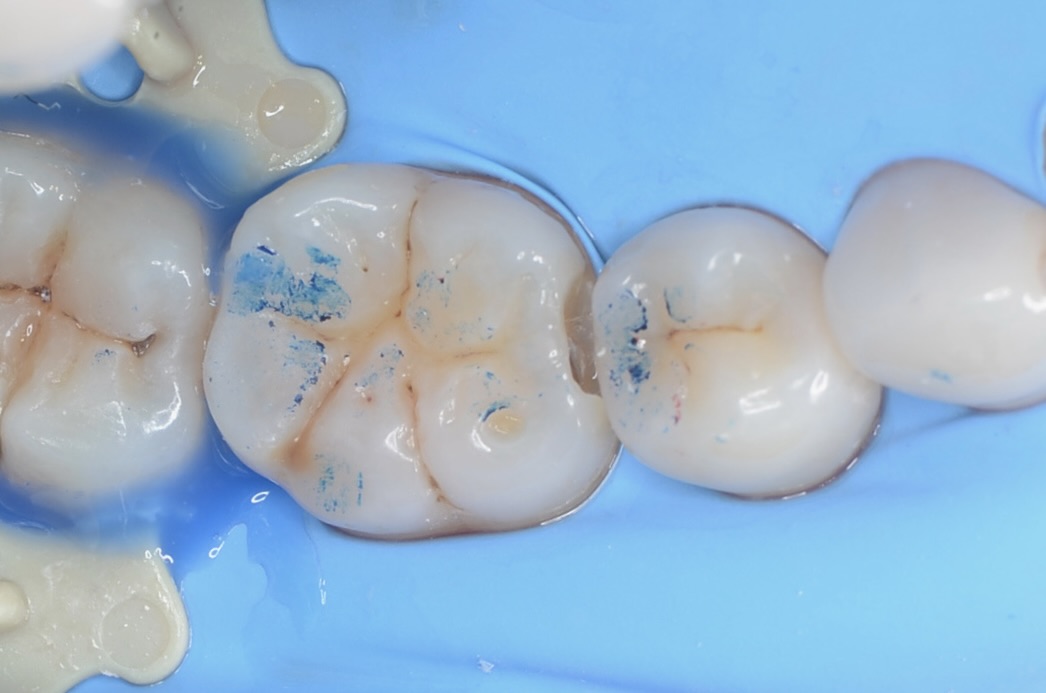

咬合接触点の確認

噛み合わせの点を印記します。できるだけ咬合接触点は削らないようにします。 -

ラバーダム装着

虫歯治療においてもラバーダム装着は必須です。 唾液や血液から歯面が汚染されるのを防ぎ、乾燥状態を保つラバーダムは、接着力を向上させるためにも大切なアイテムです。 -